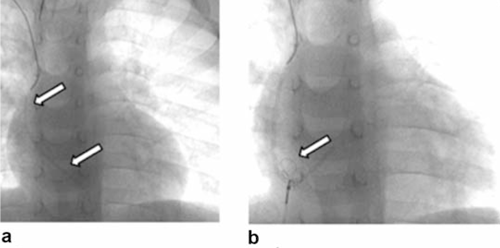

Figura 3: En a se muestra resto de catéter embolizado en arteria pulmonar rama basal izquierda, flechas. En b, c y d se muestra su extracción vía vena cava inferior, flechas.

Figura 4: En a se muestra resto de catéter procedente de vena subclavia derecha, embolizado en aurícula derecha y ventrículo derecho, flechas. Se observa su sector proximal más radioopaco, pues contiene una guía metálica en su interior. En b se muestra, flecha, su captura y extracción vía vena cava inferior.